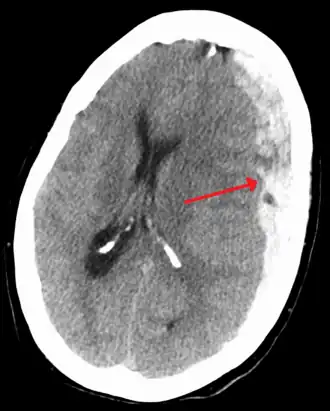

Subdural hematoma as marked by the arrow with significant midline shift

A subdural hematoma demonstrated by CT